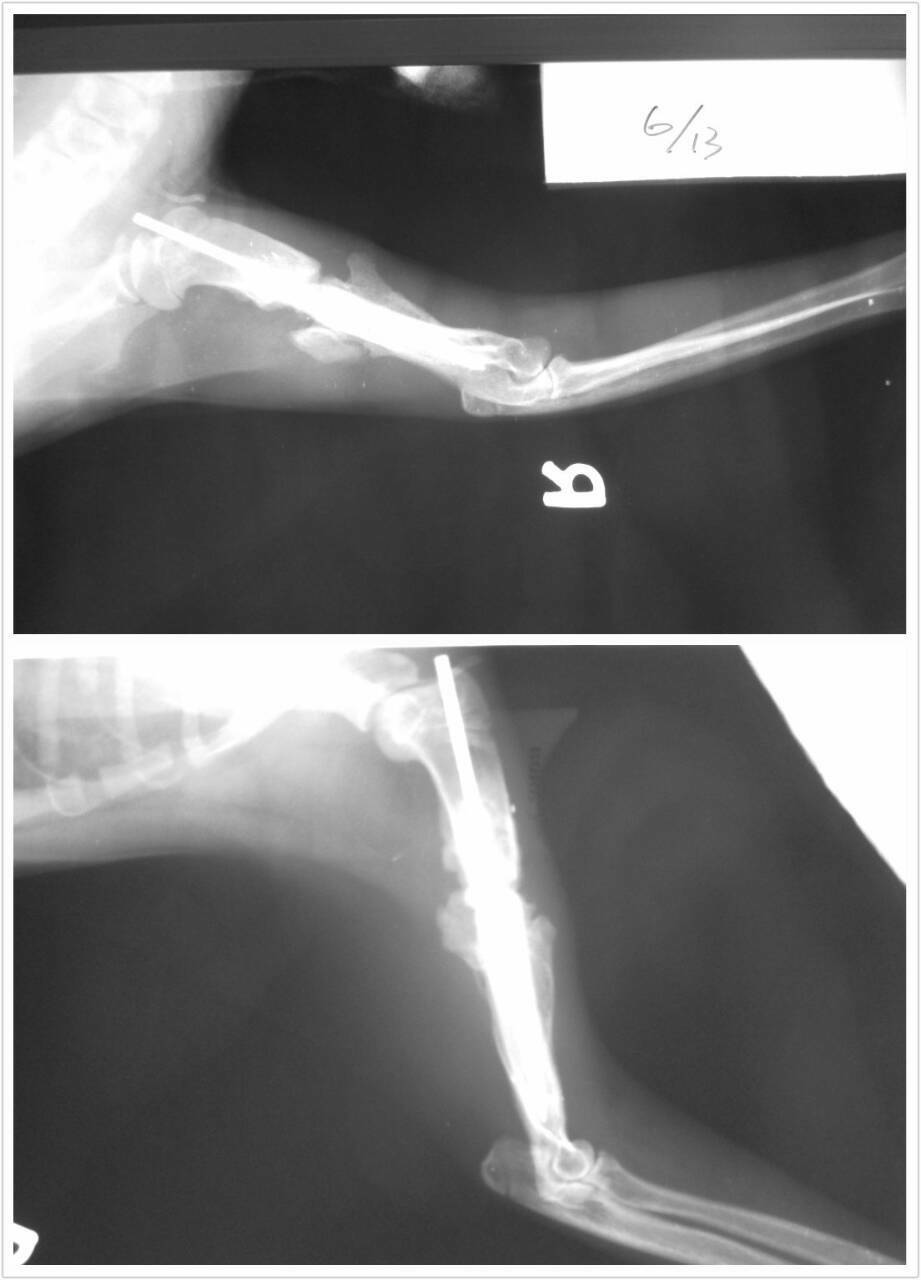

主題: 高雄壽山收容所醫務室攔截既將被安樂之花花(鼻氣管炎,右後腳外傷,右前腳膊骨斷裂非常嚴重) 申請者姓名: 張婷俞 花色: 申請日期: 2014-07-02 22:42:49 申請者部落格: 申請者臉書網址: 所在縣市/合作醫院: 高雄市/樂生動物醫院 治療費用: 28080元 需求人數: 30人 已結案 (2014-08-05 10:58:14) 報名人員: 小四 x2(已付款)、YiLing Li(已付款)、阿米(已付款)、吳佳祐(已付款)、胡嘟嘟(已付款)、鄧莉臻(已付款)、Kith Shiu(已付款)、Joanna Hu(已付款)、Sybil Huang(已付款)、Riona Chiu(已付款)、Egg(已付款)、Victoria Liou x2(已付款)、vivian(已付款)、Alice Tsai(已付款)、Victoria Liou x2(已付款)、Gina Du(已付款)、Sylvia x2(已付款)、阿曄(已付款)、Jean Lin(已付款)、Kuen-Lin Tsai(已付款)、凌波煙嵐(已付款)、Yaruh Fu(已付款)、有貓真好(已付款)、曾昭瑜(已付款)、CrystalBall x2(已付款)、 候補人員: 動物病情說明: 5/8上高雄壽山收容所救援2隻既將被安樂需要醫助的貓咪,花花跟白白。花花有脫水及眼鼻分泌物,咳嗽等鼻氣管炎的症狀且右後腳有外傷,右前腳跛行不願著地,經醫生鎮定照X光檢查,發現其上膊骨已斷裂,需手術治療,但因血液檢驗呈現白血球偏高,加上其嚴重鼻氣管炎的狀況,初步會先給藥及輸液治療,待病情穩定後再進行骨科手術。花花原本已結紮剪耳。

10 骨科手術 7000

註:因骨科手術住院天數較久,醫療費用打9折。

總共費用:28080元整

動物近況說明: 壽山花花於昨晚6�26出院,花花因為骨科手術關係,醫生說需要在關籠一個月,讓骨頭復原。目前花花關籠隔離復原中~謝謝協會跟大家幫忙花花醫助費用